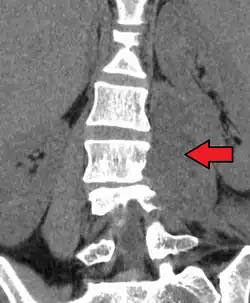

Psoas abscess

Psoas abscess is a collection of pus (abscess) in the iliopsoas muscle compartment.[1][2][3] It can be classified into primary psoas abscess (caused by hematogenous or lymphatic spread of a pathogen) and secondary psoas abscess (resulting from contiguous spread from an adjacent infectious focus).[3]

Symptoms include flank pain, fever, and an inguinal mass. A positive psoas sign should raise suspicion of psoas abscess as a possibility. Owing to the proximal attachments of the iliopsoas, such an abscess may drain inferiorly into the upper medial thigh and present as a swelling in the region. The sheath of the muscle arises from the lumbar vertebrae and the intervertebral discs between the vertebrae. The disc is more susceptible to infection, from tuberculosis and Salmonella discitis. The infection can spread into the psoas muscle sheath.[4]